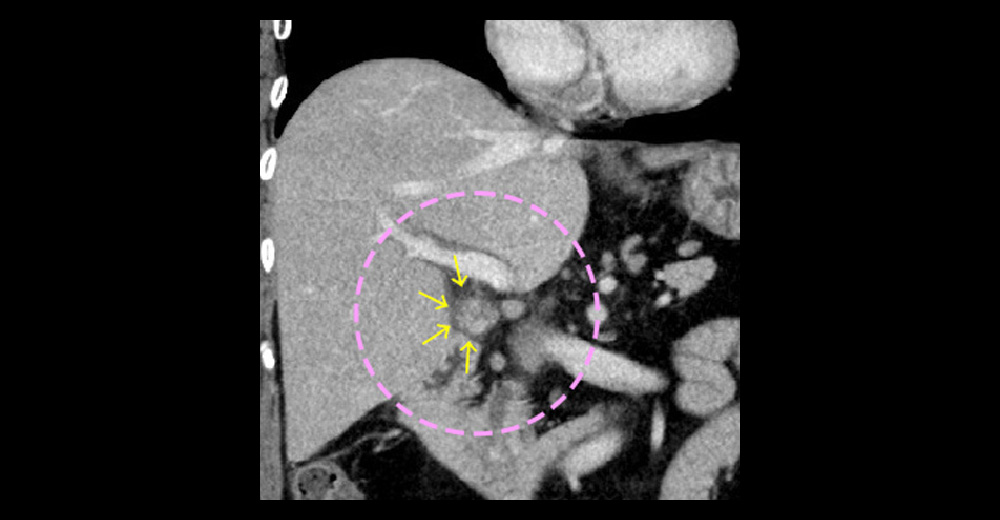

造影CT動脈相/造影CT動脈相*冠状断